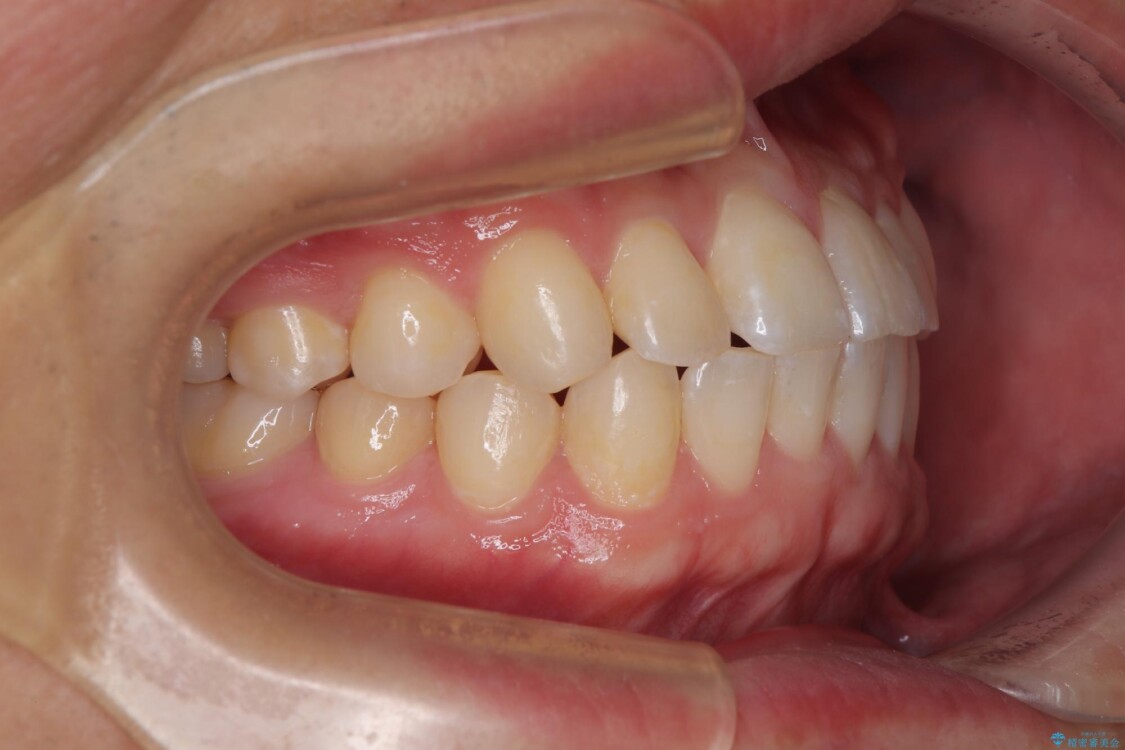

**前歯のデコボコ(叢生)**が整い、歯列全体が美しく改善

シザーズバイトの奥歯も正常なかみ合わせに改善

捻転歯も回転が修正され、全体的に清掃性・咀嚼効率が向上

治療後

• 前歯のガタガタ・奥歯のかみ合わせ(シザーズバイト)を改善|1年半で完了したメタルブラケット矯正 治療後画像